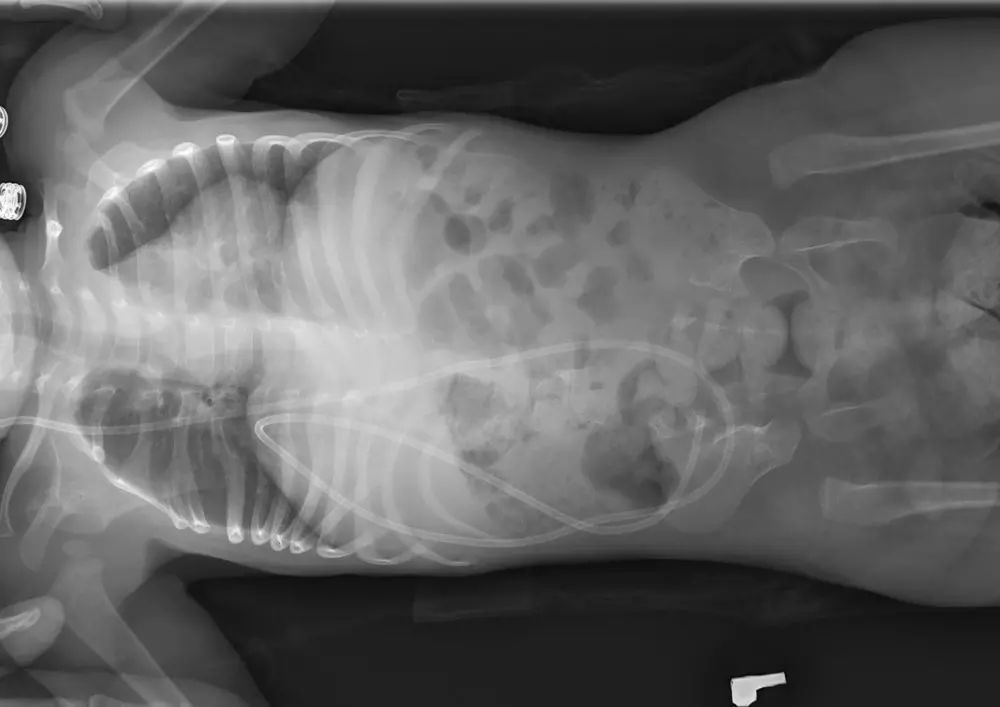

W dziale „Nowoczesne metody fizjoterapii” znajdą Państwo tekst pt. „Metoda Vojty w leczeniu przepukliny oponowo-rdzeniowej”. Mgr Ewa Żulewska-Fiks wskazuje, jak ważne jest przeprowadzenie operacji w ciągu pierwszych 72 h życia dziecka. Pomaga to uniknąć infekcji, przywrócić prawidłowe krążenie płynu mózgowo-rdzeniowego, zabezpieczyć rdzeń i otaczające go tkanki przed urazem. To również krok ku szybszemu usprawnianiu ruchowemu dziecka. Metoda Vojty jest polecana ze względu na wszechstronność, skuteczność oraz niewielki koszt leczenia z jej wykorzystaniem.